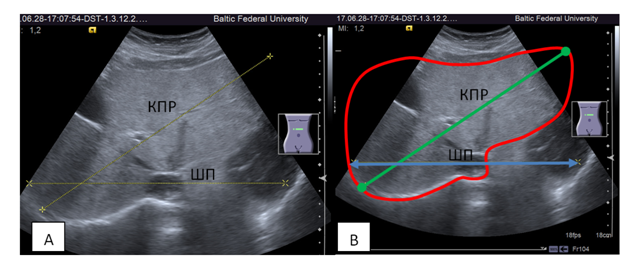

The second answer to the question why CLV formulae are not used in clinical ultrasound, is due to technical difficulties and operator-dependence of the measurement process. Four of five CLV formulae listed in table 1 use width of the liver as one of the arguments of the equation. Fig.3 demonstrates the method of measurement of the width of the liver on the specimen. To measure TransL through clinical ultrasound using convex probe in most cases is impossible (Figure 4). Even when liver has a normal size its lateral borders are outside of the working area of the monitor screen. From this point of vue, the bias of TransL measurement in clivical ultrasound is unsatisfactory high.

Figure 4 A: Ultrasound cross section of the liver trough subcostal access. ШП, width of the liver measured in horizontal plane (TransL), КПР, oblique transverse diameter (the most remote point of the right dome of the diaphragm and the left border of the liver). B: The same image. The borders of the liver are outlined. The ШП (TransL) do not fit in the image.